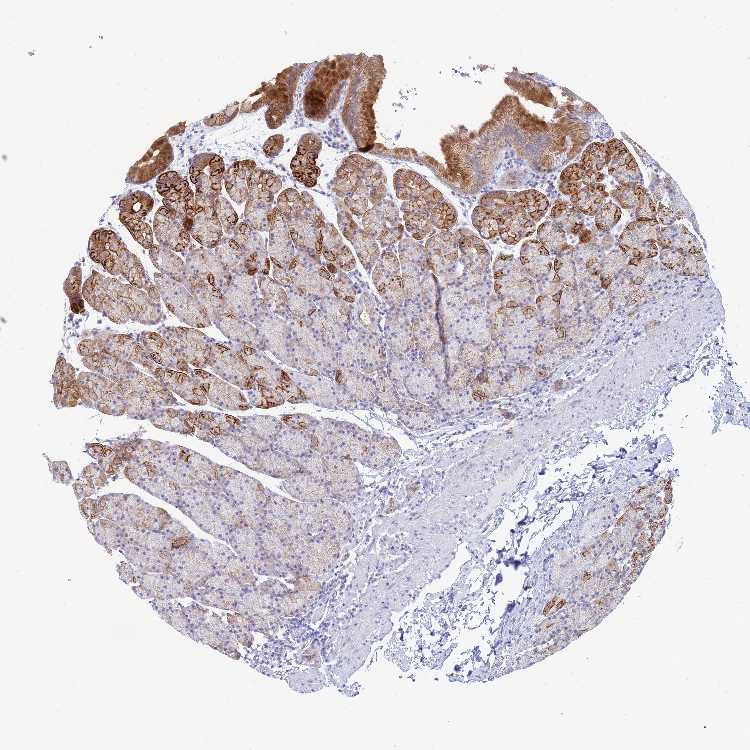

TISSUE PRIMARY DATA STOMACH Show tissue menu

STOMACH 1 - Antibody stainingi

Antibody staining in the annotated cell types in the current human tissue is reported as not detected, low, medium, or high, based on conventional immunohistochemistry profiling in selected tissues. This score is based on the combination of the staining intensity and fraction of stained cells.

Each image is clickable and will lead to virtual microscopy that enables deeper exploration of all samples and also displays staining intensity scores, fraction scores and subcellular localization as well as patient and tissue information for each sample.

Antibody HPA044933Antibody HPA053344

Glandular cells HighHigh